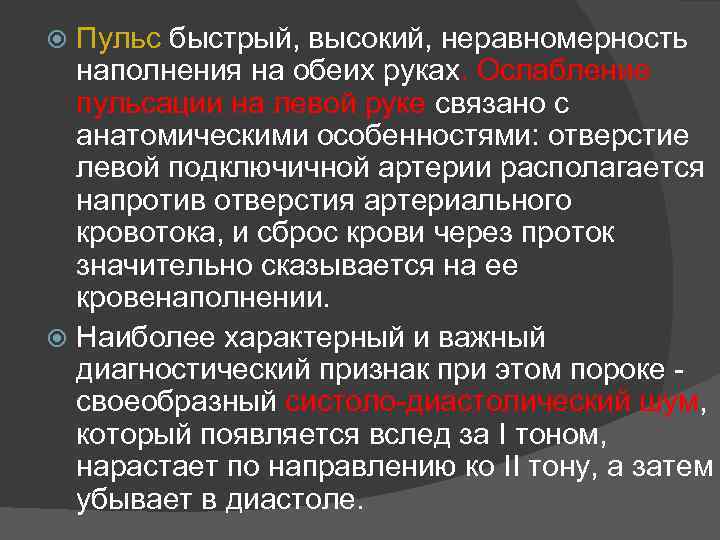

Пульс быстрый, высокий, неравномерность наполнения на обеих руках. Ослабление пульсации на левой руке связано с анатомическими особенностями: отверстие левой подключичной артерии располагается напротив отверстия артериального кровотока, и сброс крови через проток значительно сказывается на ее кровенаполнении. Наиболее характерный и важный диагностический признак при этом пороке - своеобразный систоло-диастолический шум, который появляется вслед за I тоном, нарастает по направлению ко II тону, а затем убывает в диастоле.

непрерывный систоло-диастолический шум достигает максимальной интенсивности в I-II межреберьях слева от края грудины. Шум обычно усиливается в горизонтальном положении больного, особенно резко - при сдавлении брюшной аорты вследствие повышения давления в ней. Он усиливается также при вдохе, благодаря увеличению количества крови, протекающей через артериальный проток (вследствие снижения давления в малом кругу). При выдохе шум ослабевает. Распространение шума ограничено, причем систолический компонент обладает большей проводимостью, чем диастолический. Шум распространяется на сосуды шеи, к левой ключице, в яремную ямку, меньше - в межлопаточное пространство. Значительно уменьшается' он по направлению к верхушке сердца и в подмышечную область. Не всегда можно выделить I и II сердечные тоны из сплошного систоло-диастолического шума.